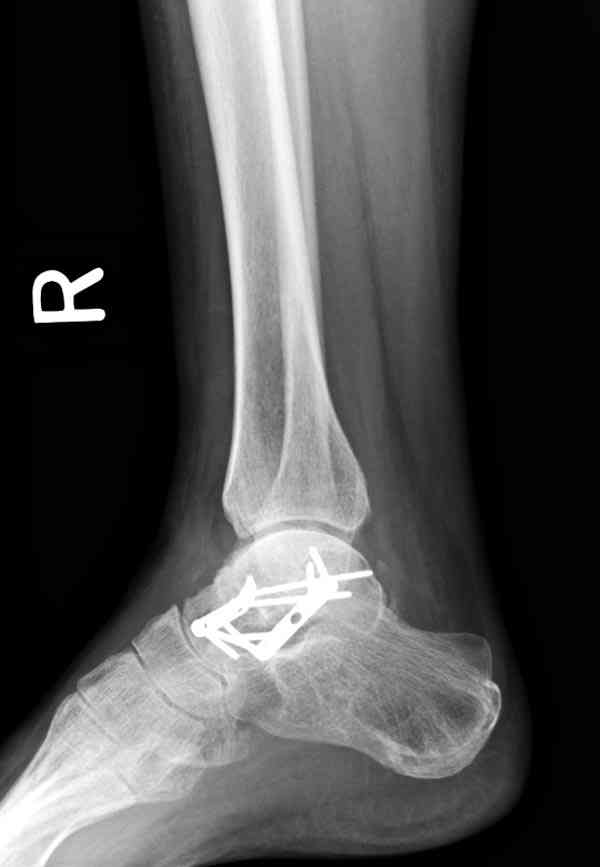

И второй случай из недавней ташкентской практики, (извините за качество ренгенограммы и только в одной проекции) случай падения с высоты (кстати моего друга - известного киноактера) - открытый

смещенный перелом тарана, с переломом переднего края дистального эпиметафиза большеберцовой кости.

При поступлении в приемной сделана первичная обработка с ушиванием открытой латеральной раны и вытяжением за пятку.

Из-за отсутствия времени пришлось оперировать на второе утро, из материала, что имеем на месте, фиксирован двумя шурупами, а третий-это контур сломанного жойстика в 4 мм. На дистальный медиальный конец тибиа antiglide 3.5 мм пластина. Через пару дней выписан и несмотря на предупреждение, самостоятельно начал нагрузку в 4 недели, время не ждет, снимается в боевике в Росийской Федерации.